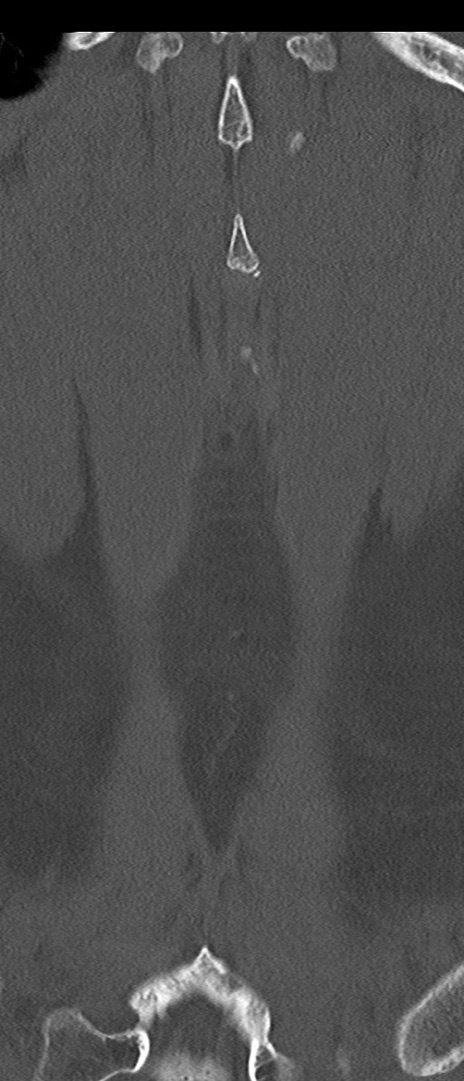

腰椎CT

矢状断像